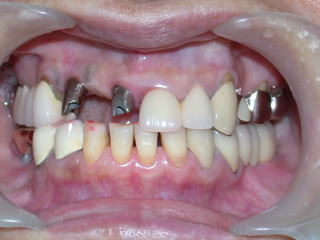

症例9:50歳代女性(新潟県長岡市要町 要町歯科 インプラント)

右上1、2、3が義歯ですが、見た目、装着感、発音など色々の不満があり、インプラントを希望しています。

こちらの患者さんは下顎両側臼歯部にもインプラントを入れており、インプラントの良い点をご自身で感じています。

唇側の骨が薄く、一部インプラントが骨外へ出ましたので人工骨骨補填材で覆います。